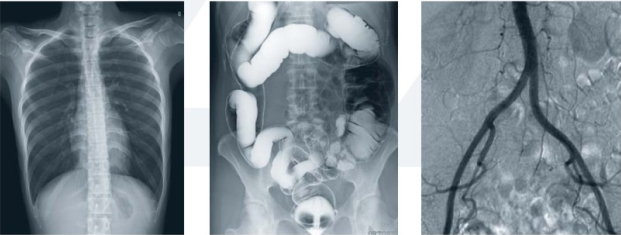

數(shù)字平板胃腸機(jī)屬于多功能X線機(jī),除具有傳統(tǒng)胃腸機(jī)所有功能外,還有DR平板探測(cè)器X線攝影所有功能,主要用于消化道對(duì)比造影、消化道吞咽造影、全脊柱拼接攝影、全下肢拼接攝影、ERCP、泌尿系造影、“T”管造影、鋇劑灌腸、四肢造影、子宮輸卵管造影等各類檢查,是檢查消化道潰瘍、腫瘤、異物等疾病的主要方法之一。

數(shù)字平板胃腸機(jī)不僅可以做普通的胃、食管鋇餐透視,胸腹部的常規(guī)透視檢查,而且圖像更清晰,多了數(shù)字化處理過程,還可以實(shí)時(shí)點(diǎn)片,更便捷的獲得實(shí)時(shí)圖像,及時(shí)抓拍住病灶圖像,為患者留存影像資料。這就像我們的手機(jī)抓拍瞬間圖像保存到手機(jī)相冊(cè)一樣,能夠診斷早期食道癌、胃癌、小潰瘍等疾病。